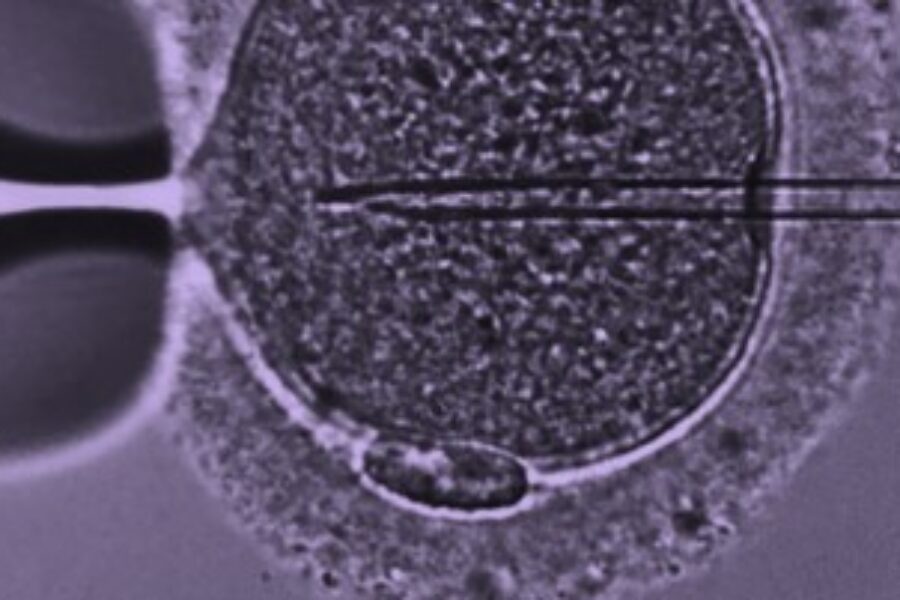

The Leeds Centre for Reproductive Medicine provides NHS fertility advice and assessment. Our partners at Care Fertility Leeds provide active fertility treatment on an NHS or self-funded basis.